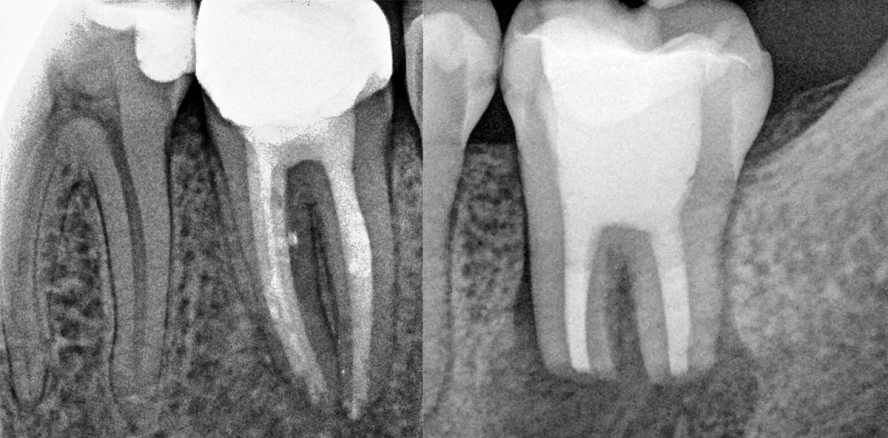

Klassisch lassen sich zahnerhaltende Möglichkeiten nach einer nicht erfolgreichen Wurzelkanalbehandlung in die konservative (also orthograde), die nichtchirurgische Wiederholung der Behandlung und die chirurgische Variante (die Wurzelspitzenresektion in all ihren Formen) einteilen. Der vorliegende Artikel will die Möglichkeiten der Entscheidungsfindung anhand der relevanten Faktoren beschreiben und einen Ausblick auf die Erweiterung der Möglichkeiten durch den Einsatz moderner mikroskopischer oder mikrochirurgischer Techniken geben.

Die Prognose der Revision von Zähnen ohne apikale Parodontitis wird mit 95 Prozent (d. h. keine Entwicklung einer apikalen Parodontitis) von mehreren Studien sehr hoch eingestuft. Bei Zähnen mit vorhandener apikaler Parodontitis findet sich eine größere prognostische Erfolgsquote von 56 bis 84 Prozent (d. h. radiologisch ausgeheilt), wobei diese Erwartungen nach Studien mit Langzeitbeobachtung angeblich noch auf 84 bis 90 Prozent steigen können (Hepworth und Friedmann 1997, Friedmann 1998, Sjögren 1990, Hoskinson 2002, Chugal et al. 2003). Interessant sind allerdings die in der bekannten Studie aus Toronto (De Chevigny et al. 2008) herausgearbeiteten präoperative Faktoren für den Erfolg einer wiederholten Wurzelbehandlung, nämlich die ursprüngliche Qualität der Wurzelfüllung (geheilt: inadäquate 88 Prozent, adäquate 66 Prozent), vorhandene Perforationen (geheilt: abwesend 87 Prozent, präsent 56 Prozent) und die radiologische Aufhellung (geheilt: abwesend 93 Prozent, präsent 80 Prozent).

Für die chirurgische Variante der Wurzelspitzenresektion lassen sich auch zusätzlich ähnliche Prognosen feststellen (Friedmann 2005), wobei die erste Spannbreite zwischen 37 und 91 Prozent Ausheilung angegeben wird, gefolgt von 33 Prozent weiterer Ausheilung nach längerer Beobachtung. 80 bis 94 Prozent der beobachteten Zähne finden sich in symptomfreier Funktion. Als positive Faktoren werden kleinere Läsionen sowie retrograde mikroskopische Techniken und Füllungen angegeben.